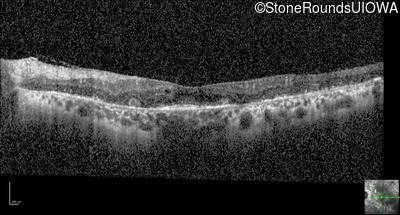

Optical Coherence Tomography - Right - 20/25

Exemplar / OCT Stack